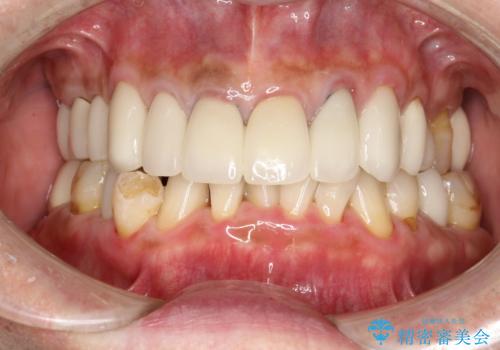

- 約1年ぶりの来院のため、着色や歯石がかなりついてしまっため、綺麗にしてほしいとのことでした。PMTC30分コースを行いました。

PMTC(保険外治療)は、毎日の歯磨きで落としきれない汚れや、コーヒ、紅茶などによる着色・タバコのヤニなどの着色も除去します。目には見えない歯と歯の間・歯肉の境目などに残っているプラーク(歯垢)もしっかり取り除きます。PMTCでは専門的な機械や材料を使用して、徹底的に汚れを除去するため、虫歯・歯周病・口臭予防などにつながります。